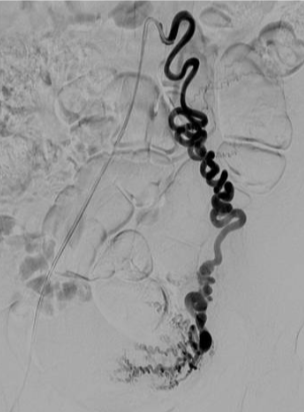

所有年龄超过 40 岁的患者, 卵巢受损 14%-43% 研究中闭经发生率(15%)与单纯UAE报告相似,可能与患者年龄(≥45岁)及卵巢储备自然下降有关。 ![]() 50岁,长期因子宫肌瘤导致月经出血过多,痛经和贫血。 子宫肌瘤栓塞术前,显示双侧子宫动脉发育不全,子宫肌瘤双侧卵巢动脉。 经皮股动脉穿刺双侧卵巢动脉栓塞,先500μm-700μm emboSphere 微球 术后4周,和6月的中短期随访,月经正常,子宫容积减少,贫血纠正,无卵巢功能衰竭。但看起来非灌注容积较少。 术后9月,由于子宫肌瘤持续存在,患者自己希望绝经,行全子宫和双侧卵巢切除术 术后病理,子宫内可见栓塞微粒伴有坏死,卵巢内也见栓塞微粒,但卵巢功能未受损。